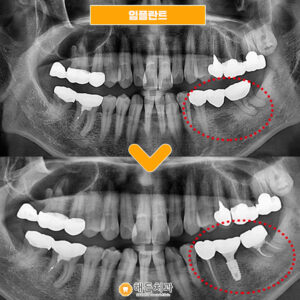

오른쪽 밑에 브릿지 크라운을 확인해 보니

브릿지 크라운이 씌워져 있던

치아의 잇몸도 꽤 내려가 있었고

그 틈 사이로 음식물이 끼면서 관리가 잘 안되어,

잇몸이 자주 붓고

불편하셨다고 말씀해주셨습니다.(ㅠㅠ)

지금도 잇몸뼈가 일부 녹아 내려간 상태라

그대로 둘 경우 머지않아

치아 흔들림, 통증 등 불편감이 생길 수 있어

기존 브릿지 크라운을 제거 후

가운데 빈자리에는 임플란트를 식립하고,

양옆의 치아에는

크라운을 따로 하나씩

씌워 주기로 결정하였습니다.

♥ 치료 전/후 ♥

(2024.04.22 ㅡ> 2024.05.28)

이렇게 기존 브릿지 크라운 제거 후

임플란트 식립과 보철물 교체로

환자분의 불편감을 해소시켜드린

사례를 소개해 드렸는데요.